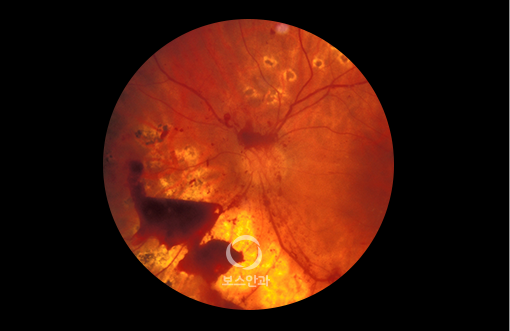

당뇨 합병증 중 가장 주의해야 하는 것이 바로 당뇨망막병증입니다.

당뇨병 경력이 30년 이상 되는 환자 약 90%에서 발병하며, 혈당 조절이 잘 안 된 경우 발병률이 더 높습니다.

망막 모세혈관이 작은 풍선처럼 커져 꽈리모양으로 변형됩니다.

비증식성 당뇨망막병증은 대게 실명을 초래하지는 않습니다.

하지만 모세 혈관벽이 약해서 물이 새어나가게 되면 황반이 붓게되어

시력 장애를 초래할 수 있습니다.

망막혈관이 폐쇄 및 손상됨에 따라 신생혈관이 망막에서 유리체를 향해

자라게 합니다. 신생혈관은 약해서 쉽게 터지고 혈액이 누출될 수 있으며,

섬유 조직과 함께 자라난 신생혈관이 수축하여 망막박리 현상이 나타날 수 있습니다.

초기에는 증상이 없으므로 당뇨망막병증이 이미 생겼어도 본인은 느끼지 못할 수 있습니다.